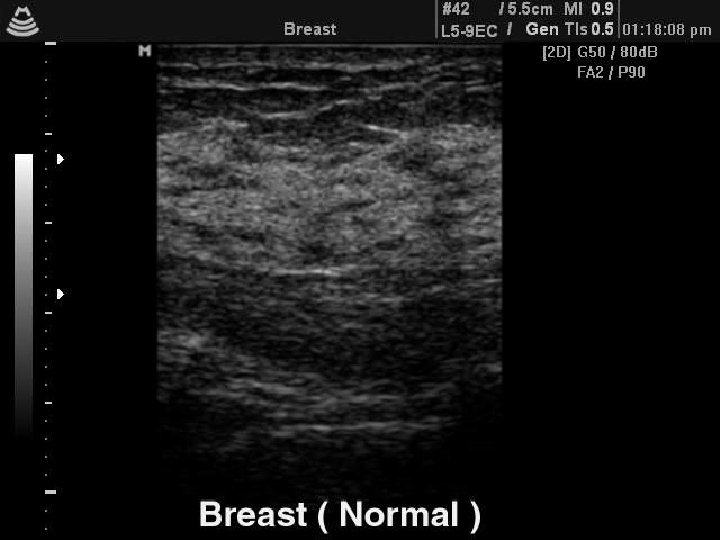

Ultrasound features of benign lumps: Respect tissue plains Long axis horizontal Wall clearly-defined Posterior brightness (cysts) Ultrasound features of malignant lumps Interrupt tissue plains Long axis vertical Wall irregular, poorly-defined Posterior shadowing